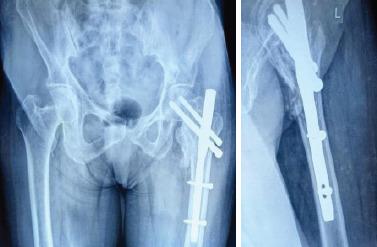

A prospective, randomized, and comparative study was conducted in a tertiary care center over a period of 18 months. One hundred patients aged 50-85 years with Boyd and Griffin type III fractures were divided into two groups. Group A (n = 50) was treated using TFN, while Group B (n = 50) received PFNA-II. Surgical techniques, post-operative care, and rehabilitation protocols were standardized. Data on operative time, intraoperative blood loss, union duration, Harris Hip scores (HHS), and complications were collected and statistically analyzed.

在一家三级医疗中心进行了一项为期18个月的前瞻性、随机对照研究。100例年龄在50-85岁的博伊德和格里芬III型骨折患者被分为两组。A组(n = 50)采用TFN治疗,而B组(n = 50)接受PFNA-II治疗。手术技术、术后护理和康复方案均标准化。收集手术时间、术中出血量、愈合时间、Harris髋关节评分(HHS)和并发症的数据并进行统计分析。